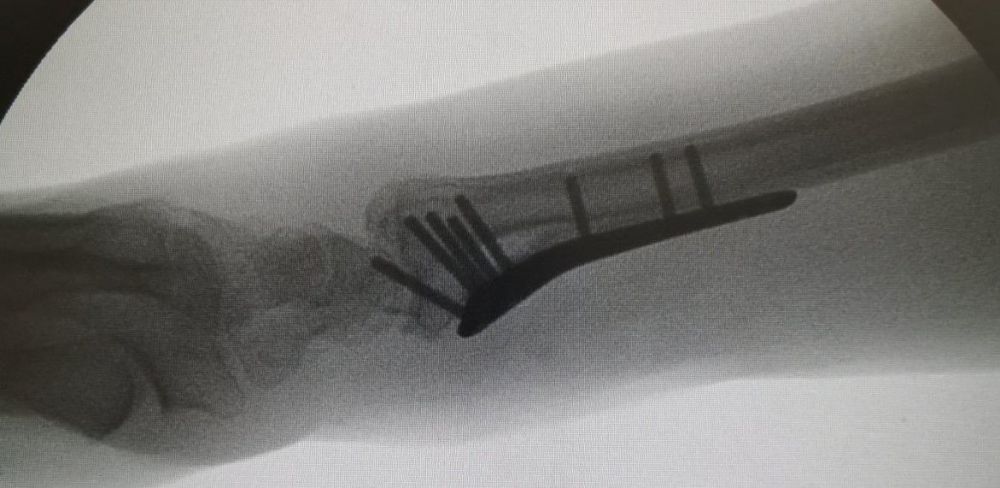

4. Displaced fracture of distal end of the right radius (wrist fracture) in a 63-year-old female.

Treatment. Open reduction internal fixation

I. Before operation, anteroposterior x-ray of the wrist II. Before operation, lateral x-ray of the wrist IIA. Day of procedure, lateral view IIB. Day of procedure, anteroposterior view